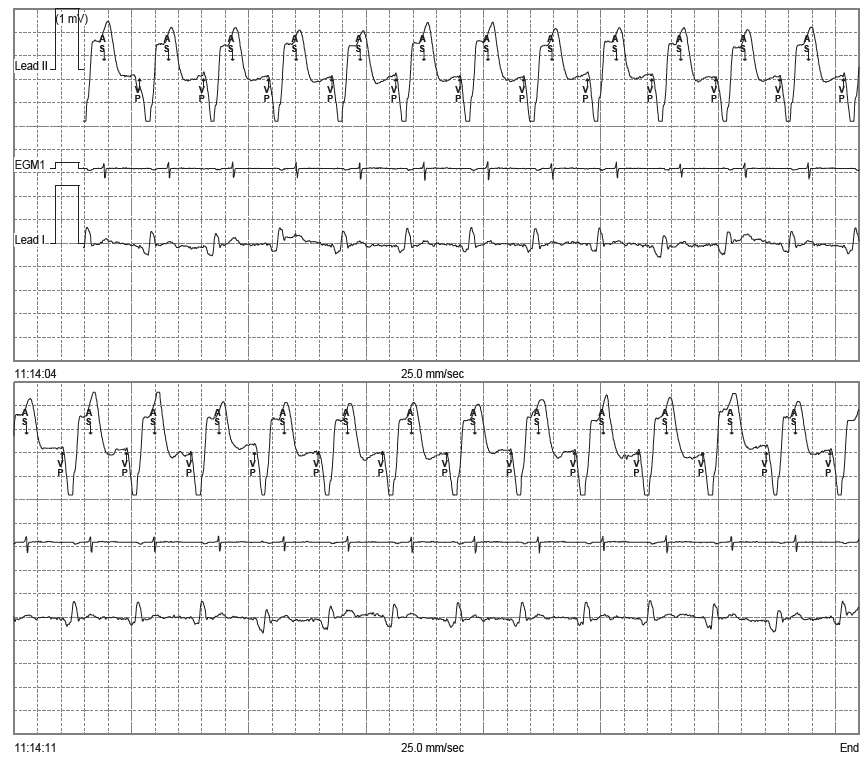

Tracé 4.9: Tachycardie par réentrée électronique

Homme de 79 ans implanté d’un stimulateur double chambre Medtronic pour bloc auriculo- ventriculaire complet; 3 jours après sa sortie, consultation aux urgences pour palpitations; enregistrement de ce tracé; programmation en mode DDD

Tachycardie à QRS large; une analyse minutieuse du tracé permet de mettre en évidence un artéfact de stimulation de petite amplitude de V3 à V5; il s’agit donc d’une tachycardie électro-entrainée (stimulation ventriculaire); différentes hypothèses peuvent être envisagées: arythmie supra- ventriculaire suivie à la fréquence maximale, tachycardie par réentrée électronique, tachycardie sinusale; l’activité atriale est difficile à identifier pour permettre d’affiner le diagnostic;

L’analyse de l’EGM permet de confirmer le diagnostic de tachycardie par réentrée électronique: succession ininterrompue de cycles VP-AS (stimulation ventriculaire, détection atriale) avec allongement du délai AV pour ne pas dépasser la fréquence maximale de suivi;

Le diagnostic électrocardiographique de tachycardie par réentrée électronique est basé sur la mise en évidence d’une tachycardie avec stimulation ventriculaire (QRS large avec artéfact de stimulation) et conduction atriale rétrograde (ondes P’ négatives dans les dérivations inférieures). Ce diagnostic peut parfois être difficile (artéfacts et ondes P’ difficilement identifiables) mais doit être systématiquement évoqué devant une tachycardie régulière à QRS large chez un patient implanté.